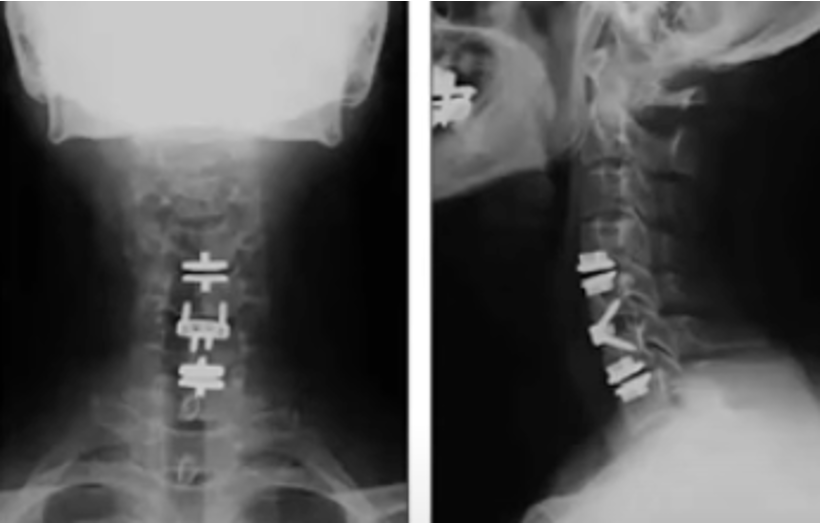

During ACDF, the damaged disc is removed, any bone spurs or disc herniations compressing the nerve or spinal cord are addressed, and then a metal spacer is placed to replace the empty disc space, sometimes with a small titanium plate to hold the bones together. Over the following months, your bone grows into the artificial spacer to connect the vertebral bodies into a single, solid segment.

ACDF has an excellent long-term track record — decades of outcomes data support its effectiveness for the right patients. It is powerful to remove compression on the nerves and spinal cord, reconstruct and re-align the bones in the neck, and increase the space between the bones to improve posture. I always say that the surgery makes the patient slightly taller and that’s true, by restoring space and alignment between the bones. The trade-off is that fusion eliminates motion at that segment of the spine permanently.

This is why a thorough evaluation — including a review of your MRI, dynamic X-rays (including flexion/extension XR), and full clinical picture — is essential before deciding between these two procedures. A surgeon who recommends one approach without carefully considering the other may not be offering you the full picture.